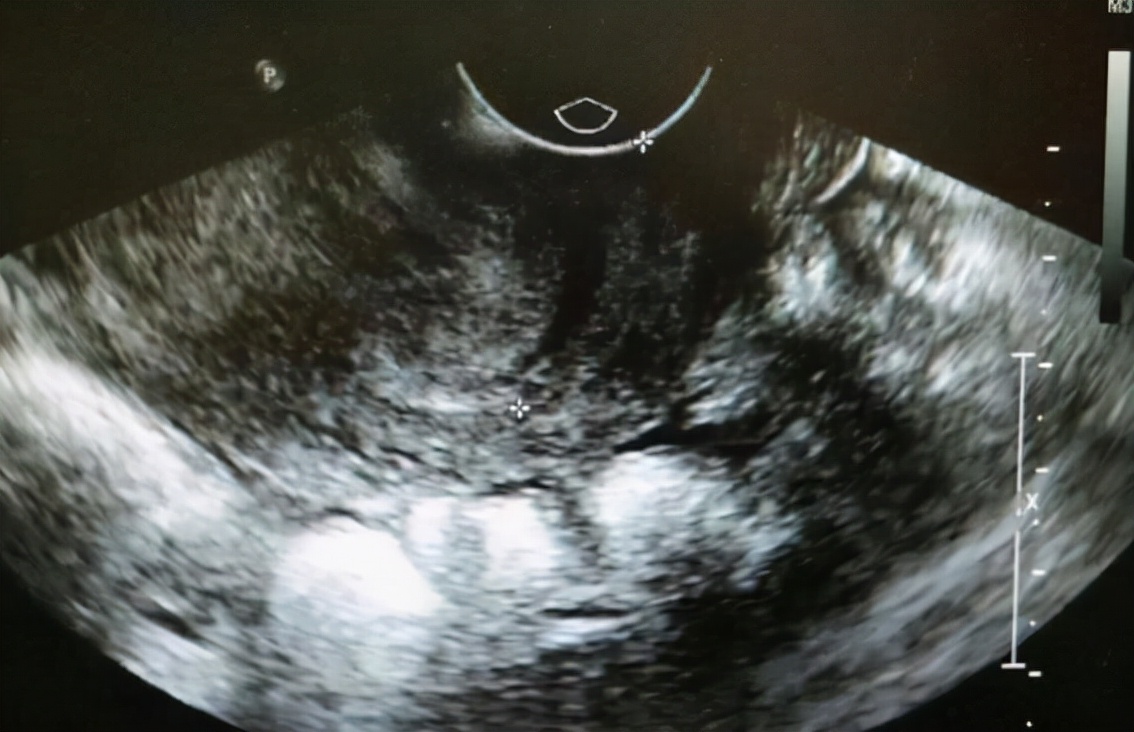

2、卵巢囊肿

卵巢囊肿指的是卵巢出现肿块,分为生理性的卵巢囊肿以及病理性的卵巢囊肿,生理性的卵巢囊肿不用治疗,需要定期复查就可以,每月月经结束到医院复查,即可消失。

病理性的卵巢囊肿无法消失,需要警惕,患者需要尽快到医院检查确定性质,如果是肿瘤,需要到医院进行切除。

卵巢囊肿不会有很明显的症状,当卵囊肿体积增大,会出现压迫感,比如腹部坠痛,卵巢囊肿多发15~50岁的女性,以及有明显家族史的人群,家族患卵巢癌以及乳腺癌的患者可进行相关的检查,结果为阳性,或囊肿速度增快,均有癌变的可能。